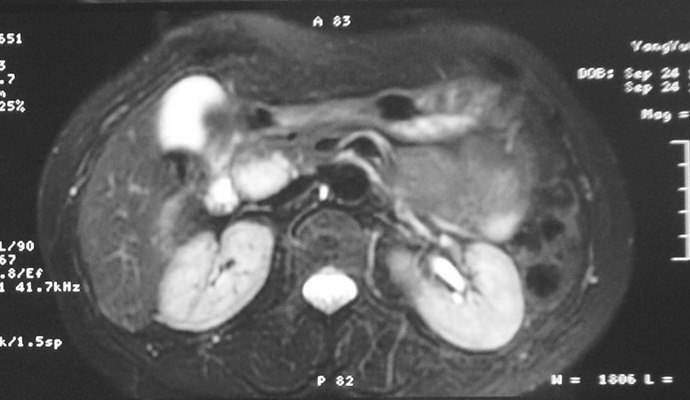

标题: MRI2066:腹膜后占位,请会诊,CT18531近期扫描图像

无明显不适,体检发现,

mri基本排除血管类肿瘤,明显强化说明极富血供,临床无症状,考虑胰岛细胞瘤可能大。

强化明显,并见有血管与之相连;考虑巨淋巴增生症.

极富血供的占位性病变,首先考虑良性,期待结果。